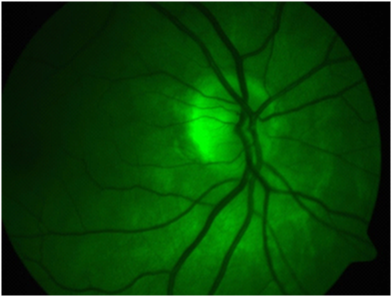

On examination her BCVA were (Figure 1) RE: 6/5+2 and (Figure 2) LE: 6/9-3, her extraocular movements were normal. There were no phorias or tropias and there was no nystagmus. Her colour vision tested with Ishihara’s colour plates was normal. The anterior segments were unremarkable and there was no RAPD. Intra ocular pressures were RE: 16 mm Hg and LE 18 mm Hg.

Figure 2 Left Eye.

LE: The left optic disc showed peripapillary atrophy and pigment clumping; corresponding to an enlarged blind spot there is anomalous branching of the central retinal vessels and mild elevation of the optic disc rim tissue. The retinal vessels are increased in number and tend to run to the peripheral retina in a straighter course than normal (Figures 2, Figure 4 & Figure 5).